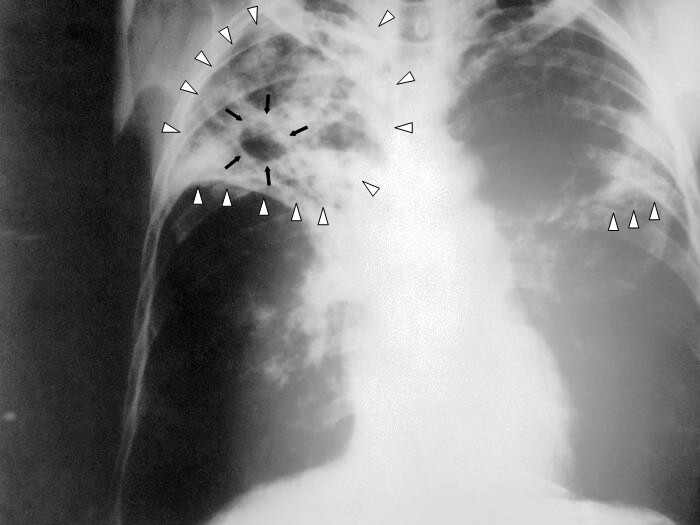

Bakterie Mycobacterium tuberculosis každý rok zahubí asi 2 miliony lidí. V posledních desetiletích se mezi kmeny bakterií tuberkulózy objevují extrémně rezistentní formy, které se pomocí dostupných léků nedají eliminovat. Při hledání Achillovy paty bakterií tuberkulózy se vědci z Albert Einstein College of Medicine zaměřili na enzym GlgE, který je podle dřívějších studií nezbytný pro růst bakterií. V lidském těle se žádná podobná molekula nevyskytuje, což znamená, že pokud by na enzym zacílila nová léčiva, nehrozily by vedlejší účinky.

Enzym GlgE je součástí enzymatické dráhy, kterou bakterie převádějí cukr trehalózu (složený ze dvou molekul glukózy) na delší řetězce sacharidů alfa-glukanů. Ty představují životně důležitý „stavební materiál“ pro buněčné struktury. Pokud se enzym GlgE zablokuje, neznamená to jenom, že bakteriím začnou chybět alfa-glukany. V bakteriálních buňkách se také začne hromadit meziprodukt enzymatické dráhy: cukr maltóza-1-fosfát. Nakonec dosáhne toxické úrovně, která poškozuje DNA. Bakterie tuberkulózy se tak sama otráví a uhyne.

Nová strategie podle vědců funguje jak na Petriho miskách, tak u pokusných myší infikovaných bakteriemi tuberkulózy. Vědci navíc zjistili, že zablokování dráhy alfa-glukanů se dá ještě „pojistit“ inaktivací dalšího enzymu Rv3032. Kombinace blokátorů obou enzymů by podle nich mohla být extrémně účinná, což znamená, že by po sobě nemusela zanechat žádné živé bakterie, u kterých by se mohla rozvinout rezistence.